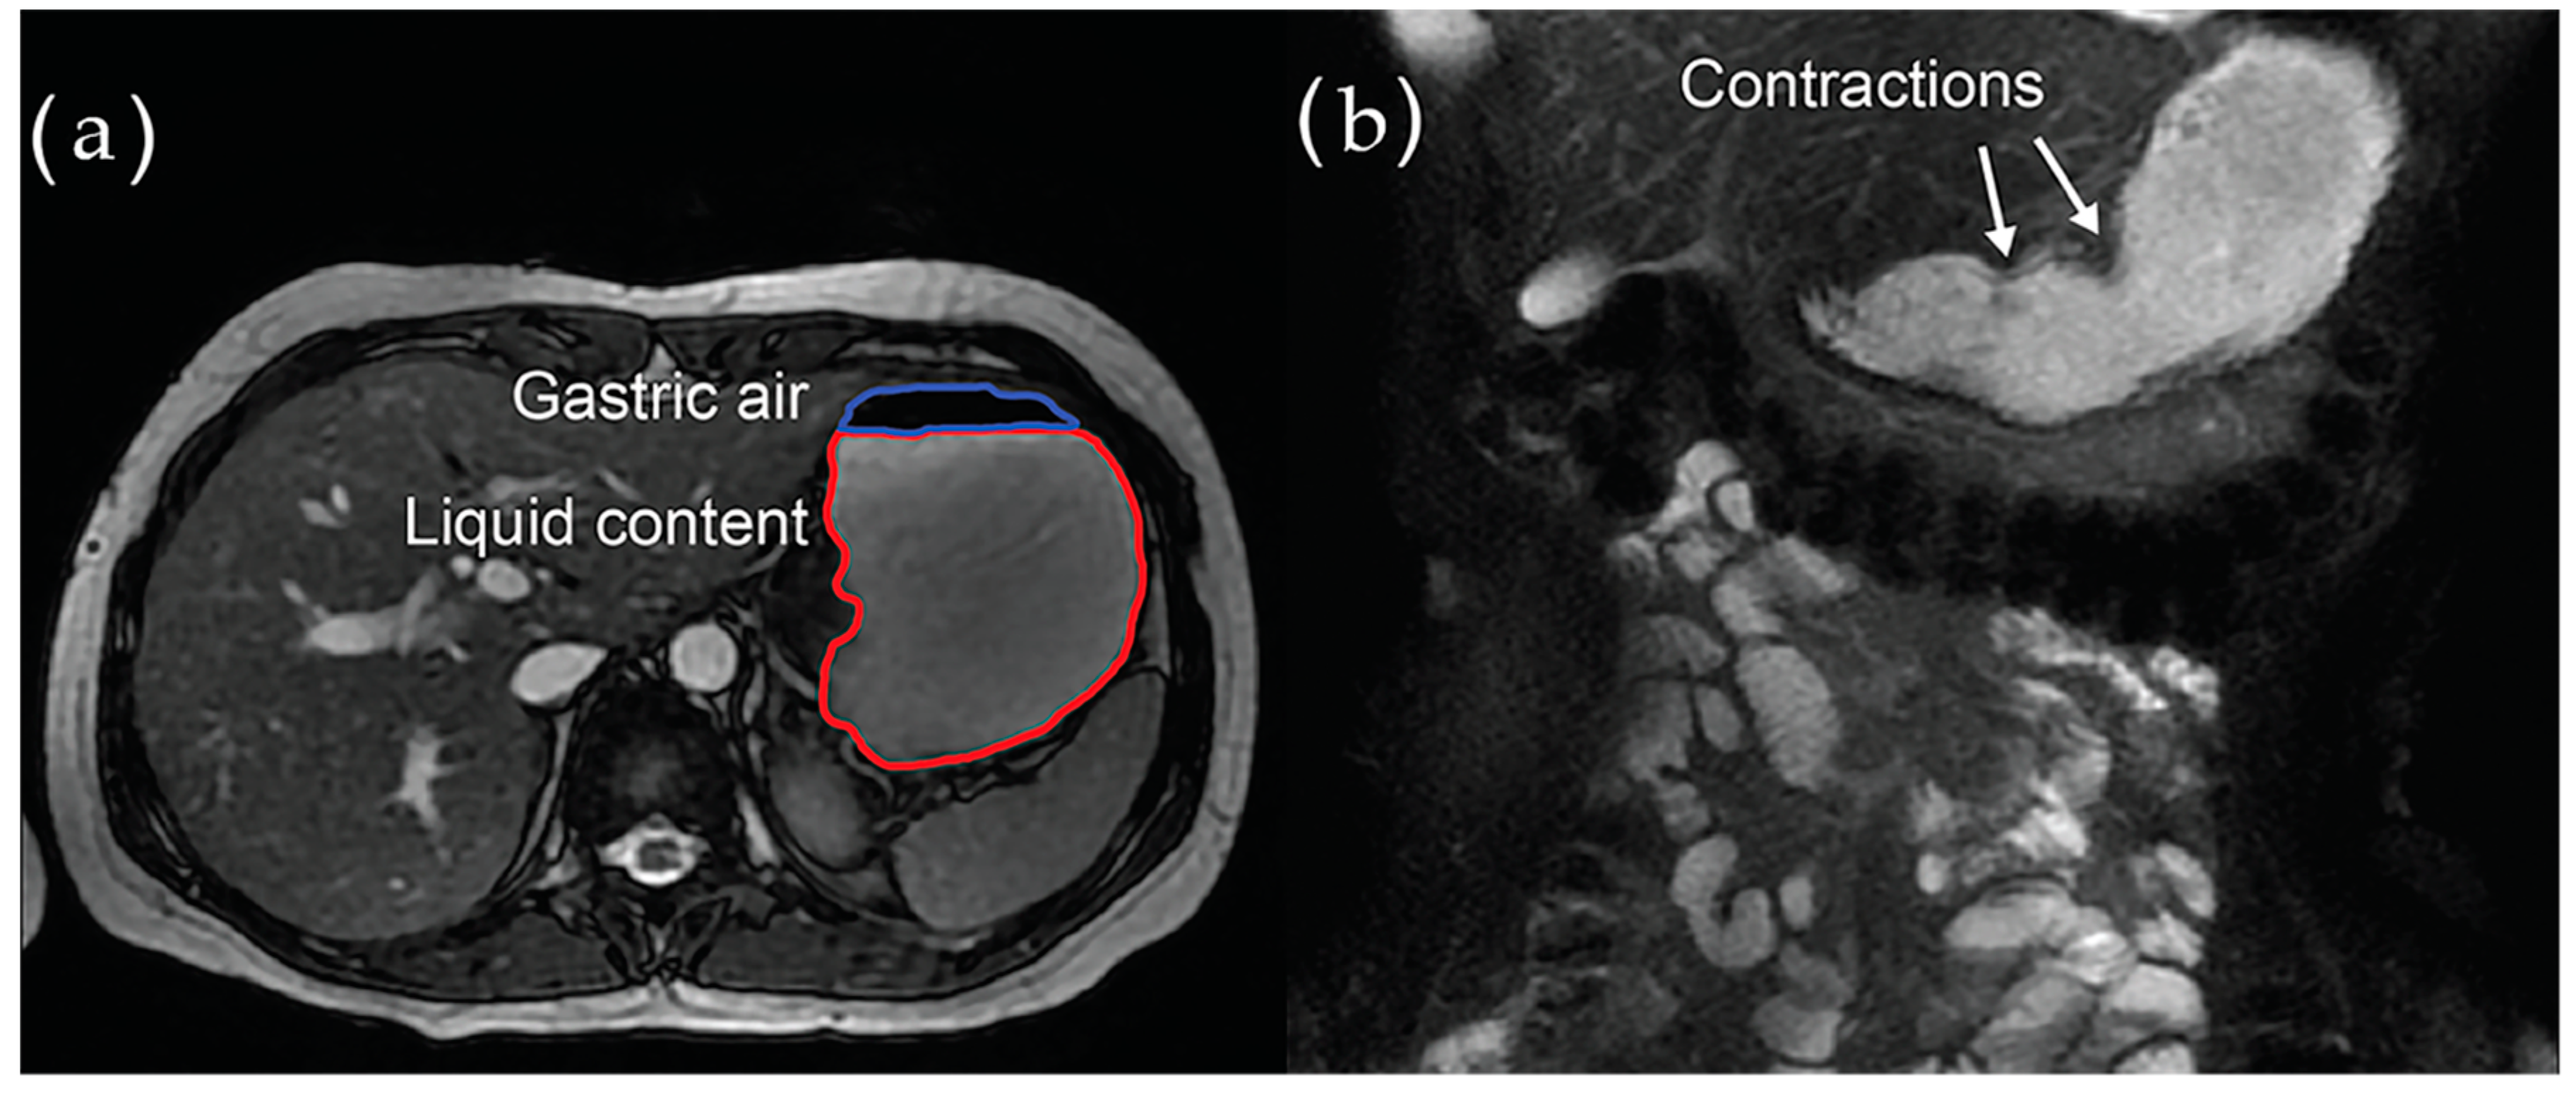

4.3.3. Magnetic Resonance Imaging (MRI)

- Banerjee, S.; Pal, A.; Fox, M. Volume and position change of the stomach during gastric accommodation and emptying: A detailed three-dimensional morphological analysis based on MRI. Neurogastroenterol. Motil. 2020, 32, e13865. [Google Scholar] [CrossRef]

- Cho, J.; Lee, Y.J.; Kim, Y.H.; Shin, C.M.; Kim, J.M.; Chang, W.; Park, J.H. Quantitative MRI evaluation of gastric motility in patients with Parkinson’s disease: Correlation of dyspeptic symptoms with volumetry and motility indices. PLoS ONE 2019, 14, e0216396. [Google Scholar] [CrossRef]

- Unger, M.M.; Hattemer, K.; Möller, J.C.; Schmittinger, K.; Mankel, K.; Eggert, K.; Strauch, K.; Tebbe, J.J.; Keil, B.; Oertel, W.H.; et al. Real-time visualization of altered gastric motility by magnetic resonance imaging in patients with Parkinson’s disease. Mov. Disord. 2010, 25, 623–628. [Google Scholar] [CrossRef]

- Froehlich, J.M.; Patak, M.A.; von Weymarn, C.; Juli, C.F.; Zollikofer, C.L.; Wentz, K.U. Small bowel motility assessment with magnetic resonance imaging. J. Magn Reson. Imaging 2005, 21, 370–375. [Google Scholar] [CrossRef]

- Ajaj, W.; Goehde, S.C.; Papanikolaou, N.; Holtmann, G.; Ruehm, S.G.; Debatin, J.F.; Lauenstein, T.C. Real time high resolution magnetic resonance imaging for the assessment of gastric motility disorders. Gut 2004, 53, 1256–1261. [Google Scholar] [CrossRef] [PubMed][Green Version]